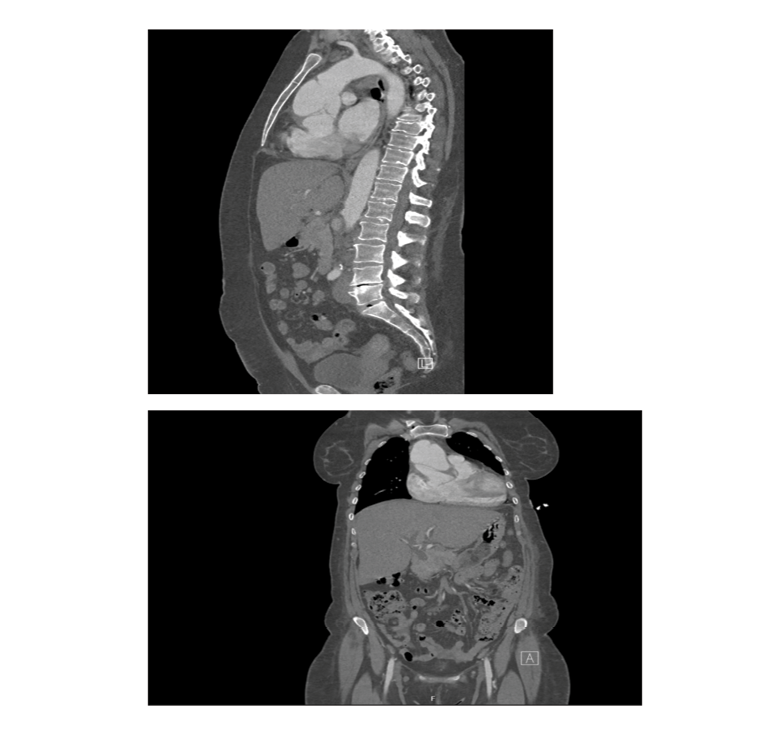

A follow-up CTA performed the following day (Figure-4) confirmed a complex Stanford type A aortic dissection with concurrent aneurysmal dilatation, measuring 6.4 cm at its widest point and affecting both the ascending aorta and aortic root. Notably, the right coronary sinus and artery were supplied by the false lumen, which clarified why the initial attempt to engage the RCA during the angiogram was unsuccessful. The dissection flap ended just before the innominate artery, with all three major cranial vessels receiving blood from the true lumen. The rest of aorta appeared normal, with no signs of contrast extravasation, and only a small right pleural effusion was noted.

An ECG was performed, revealing findings like those from her previous hospitalization. This admission resulted in a repeat CTA of the entire aorta (Figure-5), which showed that the ascending aortic dissecting aneurysm remained unchanged, measuring 6.4 cm at its largest dimension. The TTE showed normal LV size with borderline low normal function 50-54%, a hypokinetic septum, a dilated aortic root and ascending aorta with a dissecting flap, mildly dilated RV with impaired function, moderate tricuspid regurgitation, and mild aortic regurgitation.

Figure 5. CTA whole Aorta at second presentation confirmed previously diagnosed aortic dissection